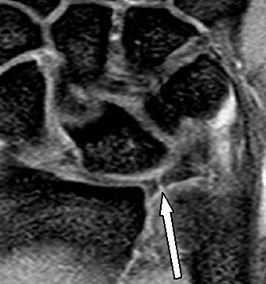

МРТ кисти. Разрыв радио-ульнарной связки – части треугольного фиброзно-хрящевого комплекса